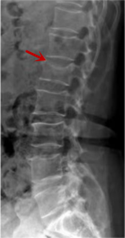

腰椎X線片作為最基礎的影像檢查手段,利于X線穿透人體組織后成像,以其快捷、直觀、價格低廉的特點,X線檢查主要包括腰椎正側(cè)位、雙斜位以及過伸過屈位。主要用于觀察腰椎骨骼的情況,如椎體是否有骨折、骨質(zhì)增生程度、生理曲度的變化、椎體移位的情況等。然而,X線檢查也有它的局限性,無法判斷是骨折的新舊,對于椎體內(nèi)部結(jié)構和周圍肌肉韌帶組織(如脊髓神經(jīng)、椎間盤、韌帶等)的顯示不佳,另外X線作為有輻射檢查,孕婦及嬰幼兒謹慎選擇。

箭頭提示腰3椎體滑脫